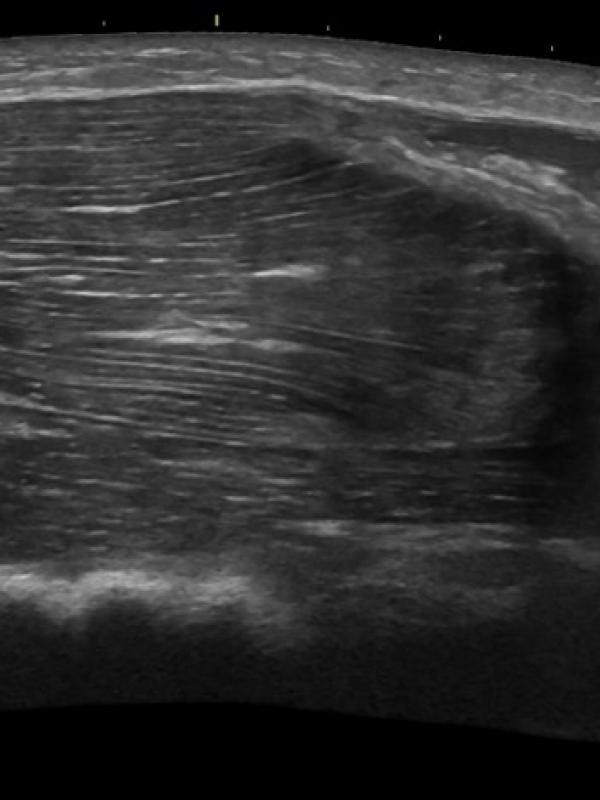

Musculoskeletal ultrasound

Musculoskeletal ultrasound (MSK)

Ultrasound imaging of tendons, ligaments, and muscle groups. Referring providers order musculoskeletal ultrasound for a number of reasons. Some common reasons are: suspicion of muscle or ligament/tendon tear or damage, trigger finger or lump.